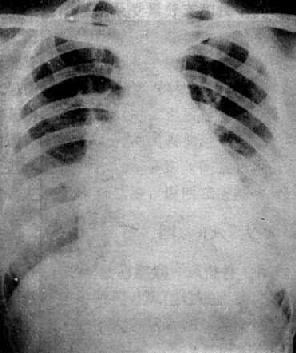

图3-2-17 慢性肺原性心脏病

心呈二尖瓣型,右心室增大,肺动脉突出,但无左心耳增大。肺动脉扩张,尤以右下肺动脉为明显,有肺门截断现象,说明有肺动脉高压。肺纹理增强,肺透明度增加,膈平而低,说明有慢性支气管炎和肺气肿